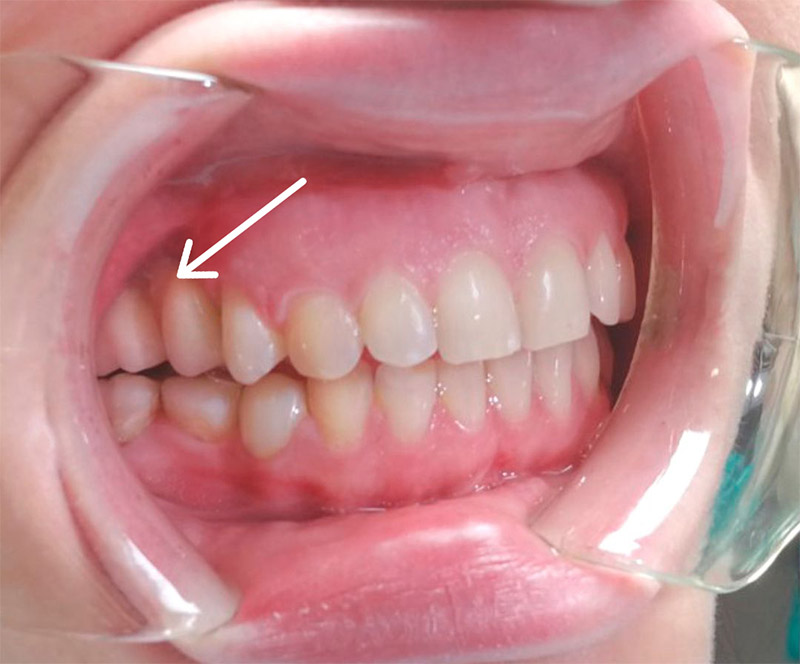

Финальное фото

- Пациент очень доволен результатом.

Общая стоимость: 238 920 ₽